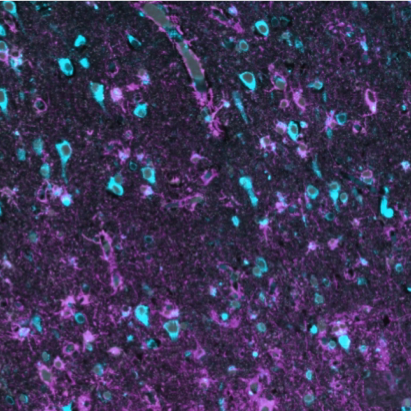

NEURODEGENERATIVE PATHOGENESIS In The Locus coeruleus

The locus coeruleus is a deeply conserved brainstem nucleus responsible for the vast amount of norepinepherine production in the brain. Morphological constraints have limited isometric scaling between the locus coeruleus and total brain size, possibly subjecting it to a great deal of oxidative and metabolic stress in large-brained animals such as humans. Several neurodegenerative diseases, including Alzheimer’s, feature early neurodegeneration in the locus coeruleus. Work done with Prof. Lea Grinberg and our group has established that the locus coeruleus is among the earliest affected regions in Alzheimer’s disease, contributes to neuropsychiatric symptom formation in Alzheimer’s disease, and is vulnerable due to unique cholesterol homeostatic mechanisms. Further work in collaboration with international consortia has leveraged the pattern of degeneration in the locus coeruleus as a novel biomarker for Alzheimer’s disease.